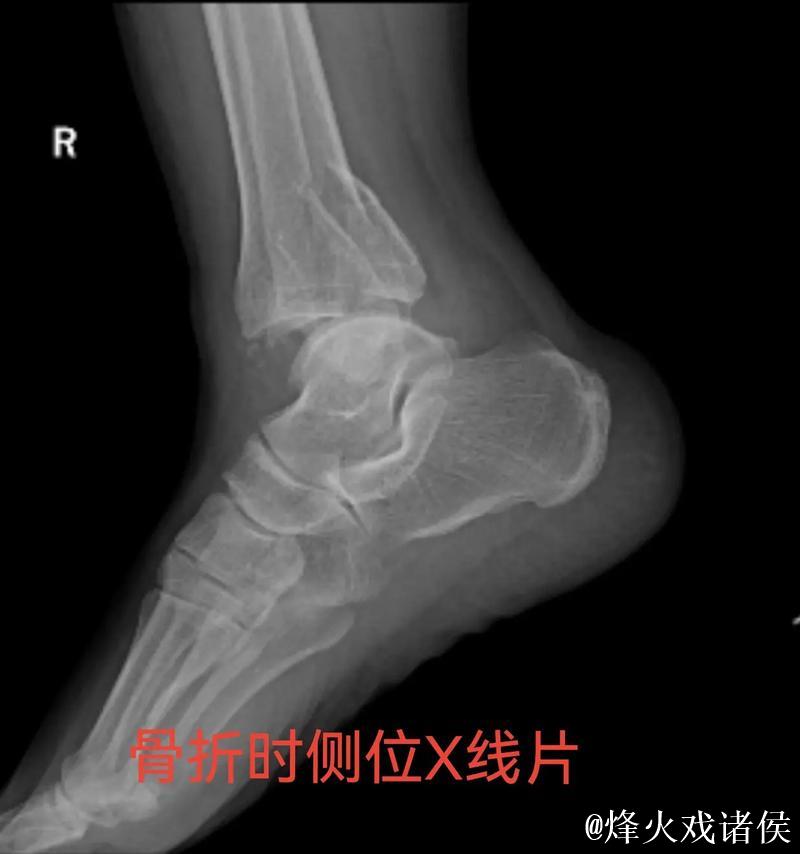

伤情解析 右踝三角韧带与腓骨骨折意味着什么

很多人在看到“右踝三角韧带断裂 右侧腓骨骨折”这样的医学表述时,只会感觉到“很严重”三个字,却未必真正理解其中的含义。踝关节三角韧带位于脚踝内侧,是一个由多条韧带组成的“组合体”,主要负责保持踝关节的内外稳定,防止小腿和足部出现异常翻转。当运动员在高速突破、急停、变向或落地时,如果脚踝遭遇过度外翻或扭转,三角韧带就可能被强行拉伸甚至撕裂。完全断裂不仅会造成剧烈疼痛,还会直接破坏踝关节的稳定性,使人几乎无法正常负重行走。与之同时出现的右侧腓骨骨折,大多与剧烈外力撞击或扭转应力有关。腓骨虽然不像胫骨那样承担大部分体重,但在踝关节的力学链条中起到重要支撑和协同作用。当韧带与骨骼在一次意外中同时受损,就意味着踝关节遭遇了极端应力,恢复与康复的难度成倍增加。

对于三角韧带断裂与腓骨骨折这种组合伤情,医学团队通常会综合评估踝关节稳定性、骨折位置与移位程度、软组织损伤范围,来决定是否采用手术治疗。若存在明显关节不稳或骨折移位,往往需要通过钢板、螺钉或钉棒内固定来重建骨性与韧带结构。在此之后,便是漫长而细致的康复周期。一般而言,骨折在数周内可以初步愈合,但韧带修复与功能恢复远比“骨头长好”更复杂。康复过程需要一套循序渐进的计划:早期的消肿与被动活动、中期的肌力与本体感觉训练、后期的专项运动模拟。每一个阶段若处理不当,都可能导致关节僵硬、力量不足或反复崴脚等后遗症。对职业运动员来说,问题不仅是“能不能走路”,而是“能不能继续高强度比赛、能不能保持原有水平”。任何轻微的落差,都可能在激烈竞争的职业舞台上被放大。